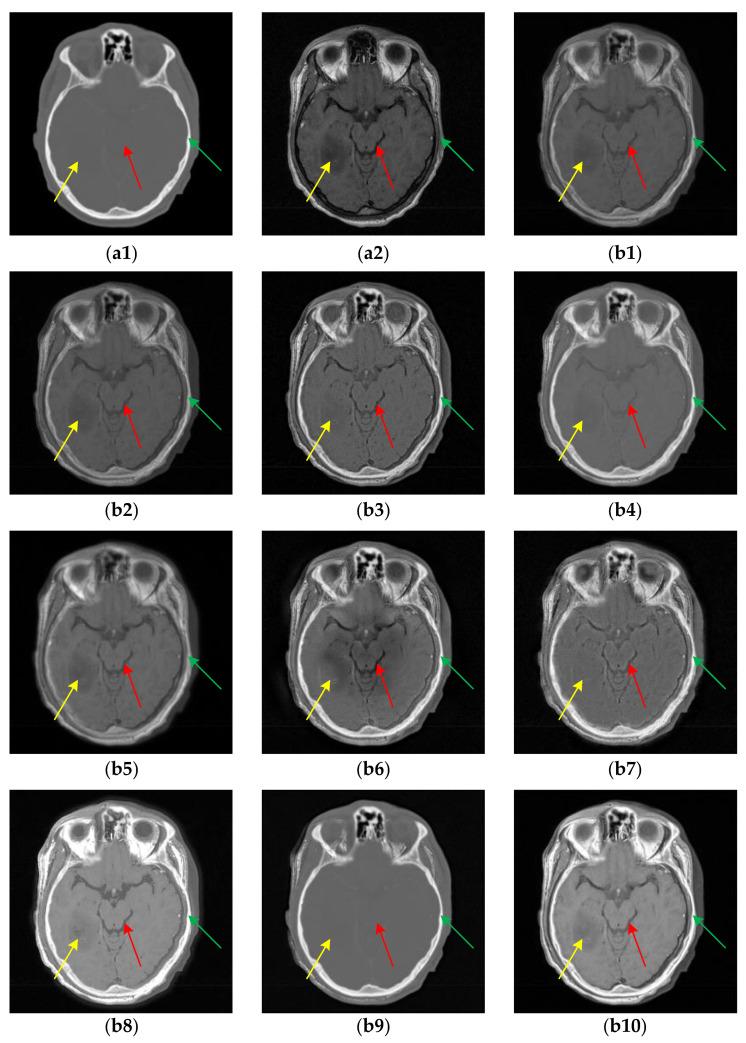

Multi-modal medical image fusion (MMIF) is crucial for disease diagnosis and treatment because the images reconstructed from signals collected by different sensors can provide complementary information. In recent years, deep learning (DL) based methods have been widely used in MMIF. However, these methods often adopt a serial fusion strategy without feature decomposition, causing error accumulation and confusion of characteristics across different scales. To address these issues, we have proposed the Coupled Image Reconstruction and Fusion (CIRF) strategy. Our method parallels the image fusion and reconstruction branches which are linked by a common encoder. Firstly, CIRF uses the lightweight encoder to extract base and detail features, respectively, through the Vision Transformer (ViT) and the Convolutional Neural Network (CNN) branches, where the two branches interact to supplement information. Then, two types of features are fused separately via different blocks and finally decoded into fusion results. In the loss function, both the supervised loss from the reconstruction branch and the unsupervised loss from the fusion branch are included. As a whole, CIRF increases its expressivity by adding multi-task learning and feature decomposition. Additionally, we have also explored the impact of image masking on the network's feature extraction ability and validated the generalization capability of the model. Through experiments on three datasets, it has been demonstrated both subjectively and objectively, that the images fused by CIRF exhibit appropriate brightness and smooth edge transition with more competitive evaluation metrics than those fused by several other traditional and DL-based methods.

多模态医学图像融合(MMIF)对于疾病诊断和治疗至关重要,因为从不同传感器收集的信号重建的图像可以提供互补信息。近年来,基于深度学习(DL)的方法已广泛应用于MMIF。然而,这些方法通常采用无特征分解的串行融合策略,导致误差累积和不同尺度特征的混淆。为了解决这些问题,我们提出了耦合图像重建与融合(CIRF)策略。我们的方法将图像融合和重建分支并行,通过一个公共编码器连接。首先,CIRF使用轻量级编码器分别通过视觉Transformer(ViT)和卷积神经网络(CNN)分支提取基础特征和细节特征,两个分支相互作用以补充信息。然后,两种类型的特征分别通过不同的模块进行融合,最后解码为融合结果。在损失函数中,既包括来自重建分支的监督损失,也包括来自融合分支的无监督损失。总体而言,CIRF通过添加多任务学习和特征分解提高了其表达能力。此外,我们还探讨了图像掩码对网络特征提取能力的影响,并验证了模型的泛化能力。通过在三个数据集上的实验,主观和客观地证明了,与其他几种传统方法和基于DL的方法融合的图像相比,CIRF融合的图像具有适当的亮度和平滑的边缘过渡,评估指标更具竞争力。